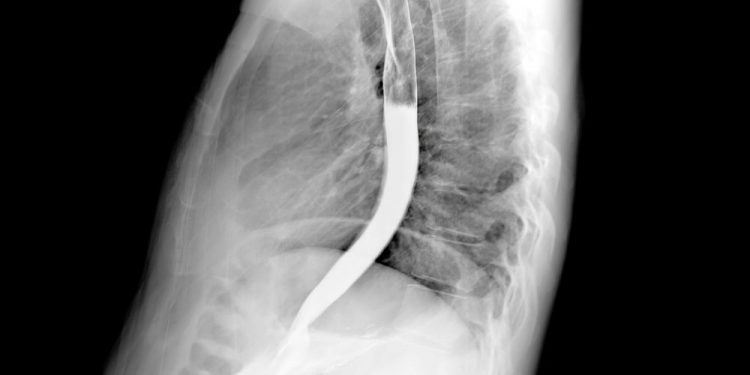

The outlook, or prognosis, for esophageal cancer depends on several factors, including the stage (how far the cancer has spread) and your general health. Your doctor will evaluate your symptoms and perform tests to check for esophageal cancer. These may include a throat examination, an endoscopy or barium swallow, and a chest X-ray. Often, doctors will also use CT scans, an ultrasound or a positron emission tomography (PET) scan, and thoracoscopy or laparoscopy to see how the cancer has affected the surrounding tissues and organs.